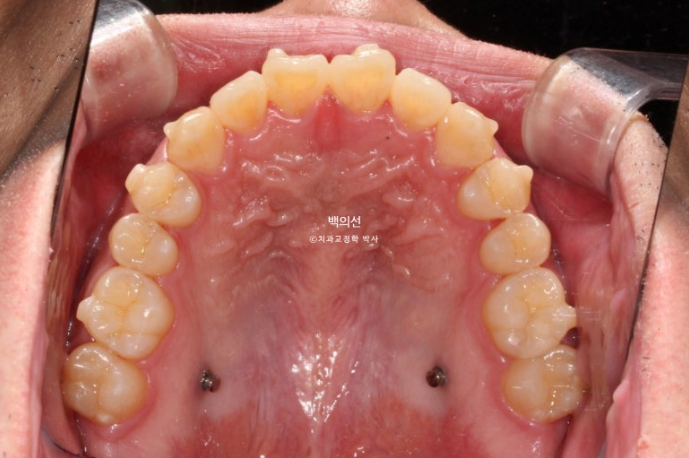

교합면 사진에서 나비치아와 바깥으로 나가있는 두번째 큰어금니가 잘 보입니다.

파란 화살표 치아끼리 엇갈려 물리는 가위교합으로 교합이 안되는 상태입니다.

특히 아래 두번째 큰어금니는 쓰러져 있습니다.

노란선이 쓰러져 있는 큰어금니죠. 사랑니를 빼고 세워야 합니다.

문제의 쓰러진 큰어금니는 앞의 큰어금니에 걸려있는 상태로, 인비절라인 투명교정장치 만으로 세우기는 힘들어요.